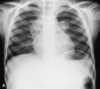

80

What does this CXR show?

* Right mainstem intubation